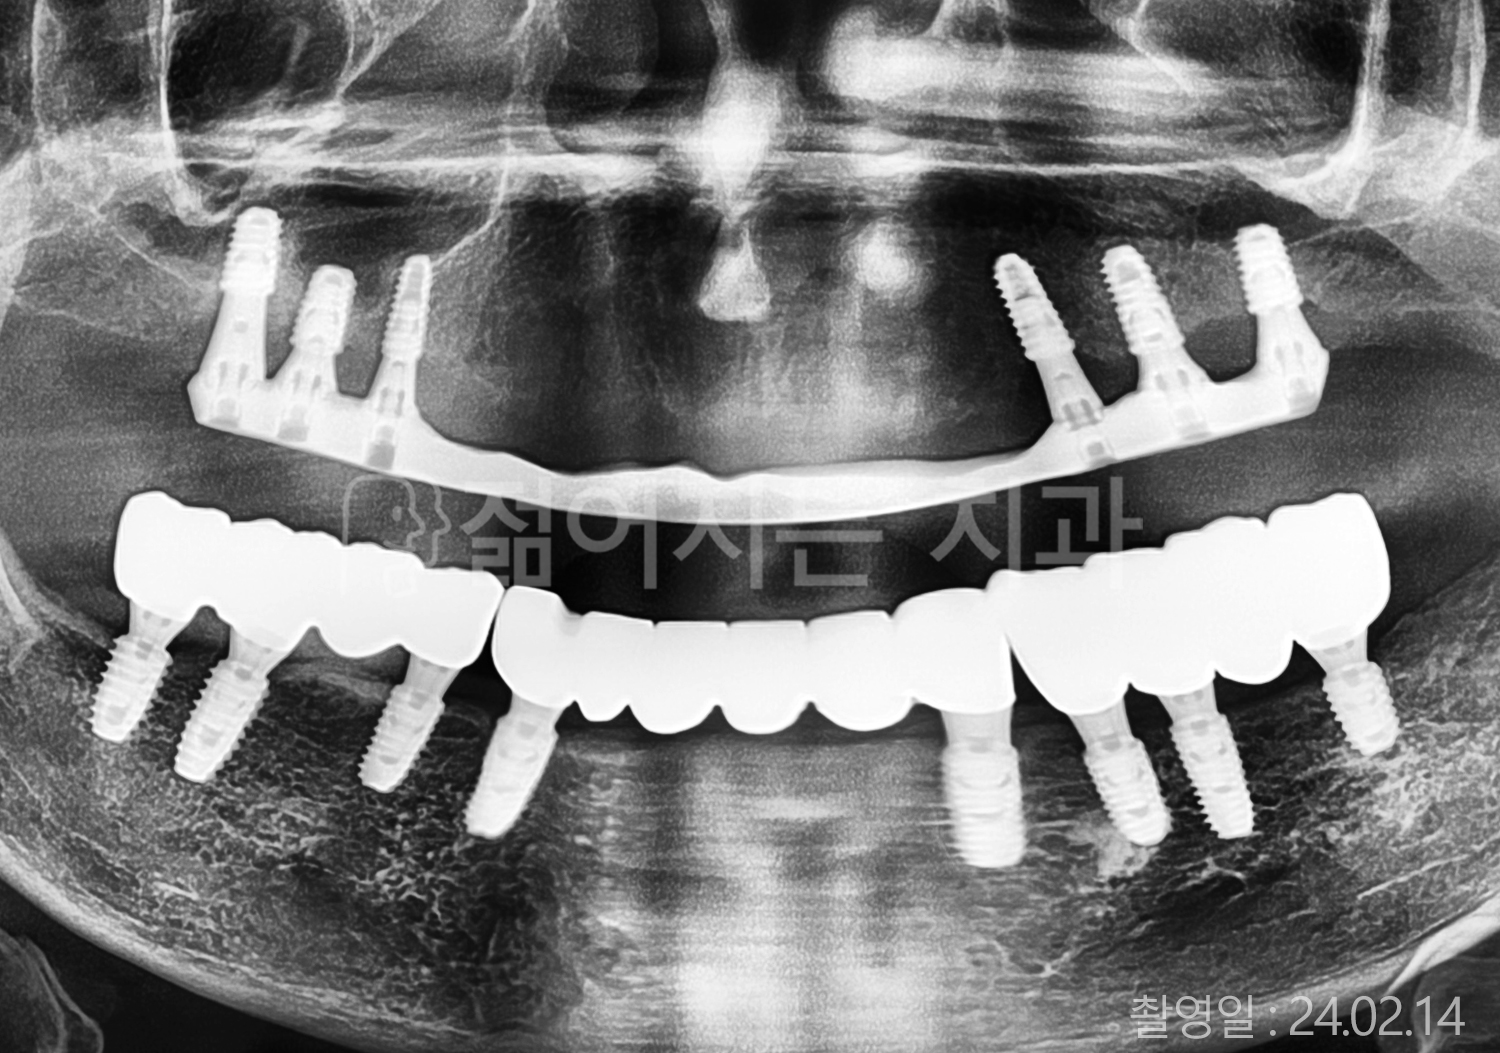

• 50대 고혈압, 당뇨, 고지혈증 전체치아 10개 이상 임플란트

• 60대 골다골증, 간경화 전체치아 10개 이상 임플란트

• 60대 고혈압, 고지혈증 전체치아 10개 이상 임플란트

• 50대 고혈압, 당뇨 전체치아 10개 이상 임플란트

• 60대 고혈압 전체치아 10개 이상 임플란트

• 60대 전체치아 10개 이상 임플란트

• 60대 고지혈증 전체치아 10개 이상 임플란트

• 40대 전체치아 10개 이상 임플란트

• 70대 전체치아 10개 이상 임플란트